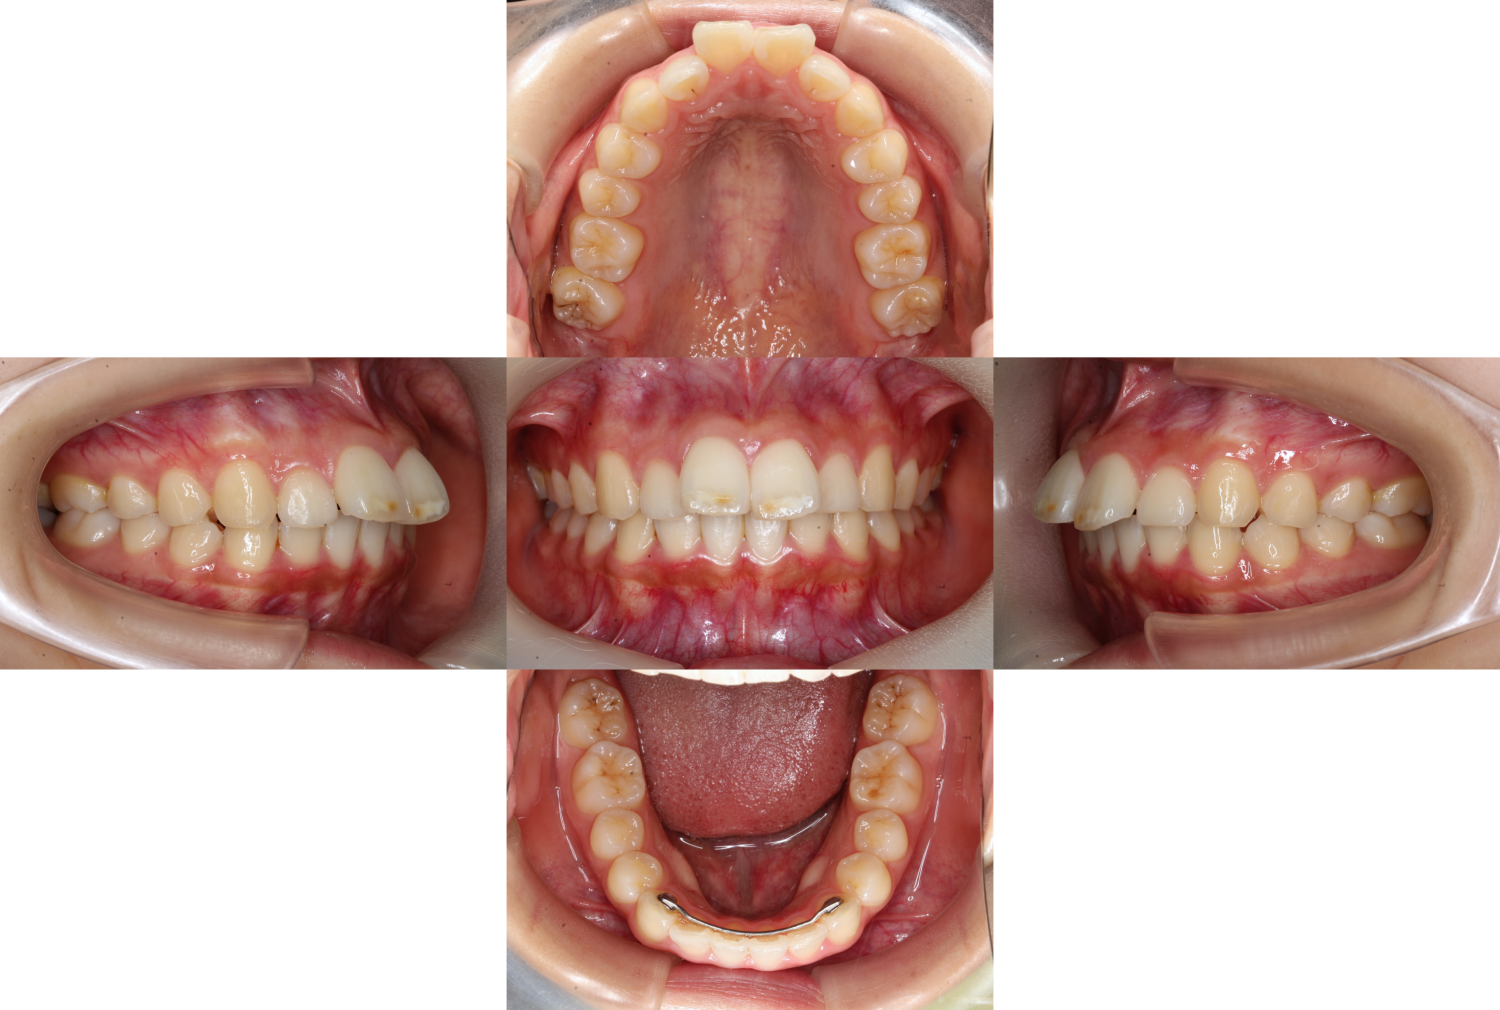

小中学生の頃に他院で矯正をしていた患者様です。

下の前歯の裏側には後戻り防止のワイヤーがついているので

キレイに見えますが、上の前歯は【後戻り】してしまっています。

こちらの患者様は矯正していたのが小中学生の頃なので

顎の成長も相まって歯並びが変化してしまったようです。

| 主訴 | 上の歯が出ている、矯正後の後戻り |